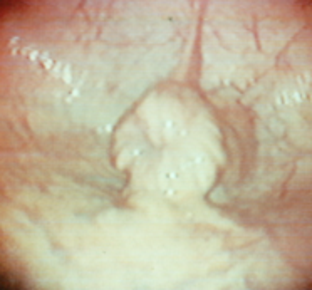

end oestrus

dioestrus

Healthy endometrium

whats included in a gynaecological exam? examination of the vulval seal, a clitoral swab, examine the vagina and cervix, endometrial bacteriology and cytology (possibly biopsy), a rectal exam, endoscopic exam, ultrasound exam and a blood sample for hormone and chromosome analysis.